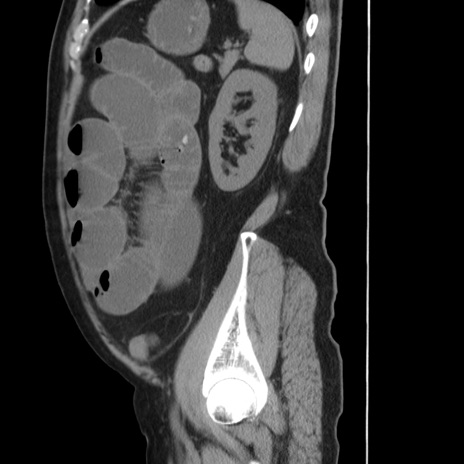

症例20(矢状断像)

【症例】 60歳代男性

【主訴】 腹部膨満、嘔吐

【現病歴】5日前頃より倦怠感を認め食事量減少し4日前の朝嘔吐、食事摂取困難となった。 3日前近医受診し点滴施行され整腸剤などを処方された。 当日他院を受診し、腹部膨満著明、炎症反応の上昇(CRP10.8、WBC11200)あり、紹介受診となる。

【身体所見】 意識JCS1 受け答えがはっきりしないBP 111/57mHg、 P 67bpm、、BT35.2°C、SpO2 97%(RA)、 腹部:膨隆、打診で鼓音あり、全体的に圧痛有り、腸蠕動音(-)、反跳痛ははっきりせず。

【データ】WBC 11400、CRP 14.20